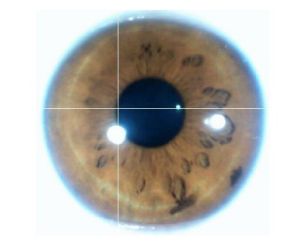

3、虹膜七環反應全圖:①胃環 ②腸環 ③自主神經環 ④內臟器官腺體環⑤內臟器官環 ⑥淋巴環 ⑦皮膚環

虹膜1、虹膜的顏色:主要有藍色及褐色,其他顏色都是混合而成。依照顏色可粗略做體質區分,藍色屬酸性體質褐色屬膽汁體質,其他還有虹膜上會出現褐色或異常色素沉澱,根椐出現的部位有不同的意義。

2、構造:基本可分為絲狀、亞麻布狀、網狀等等,主要是以纖維緊密的程度來區分,越緊密的體質越強壯。此外,纖維出現破洞或異常排列都是病態的表現。

虹膜1、發炎期:出現在虹膜的各部位,呈金黃色,表示體內有發炎的症狀。

2、次發炎期:區域呈茶褐色。

東方虹膜自然醫學會-丁娟與澳洲虹膜醫師Diaer3、慢性期:暗褐色,表示該反射區組織器官已有功能衰退的現象。

4、退化期:呈深黑色,表示該反射組織器官大部分已失去功能,亦有可能會形成組織病變,尤其應注意腫瘤的形成。